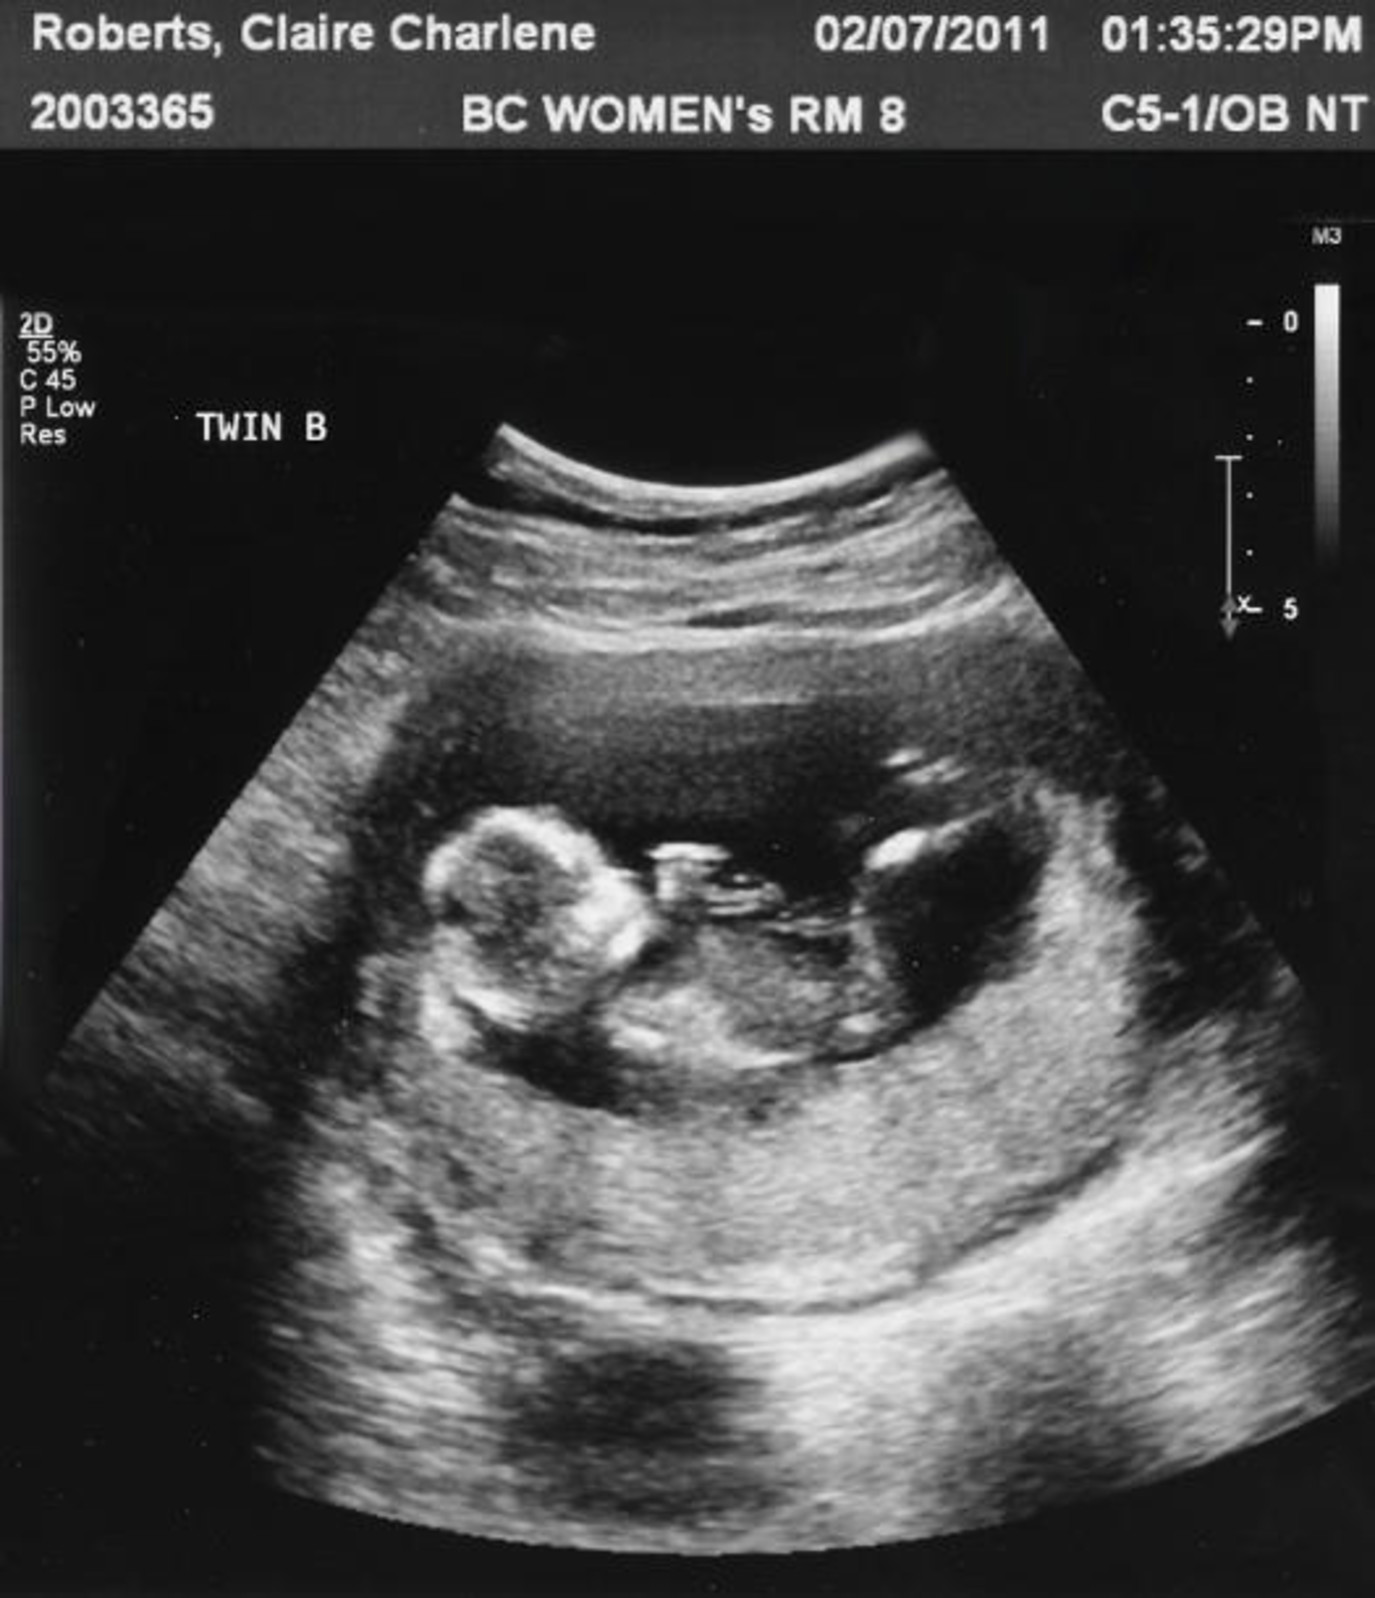

Влиять плод узи

Влиять плод узи 110 фотографий